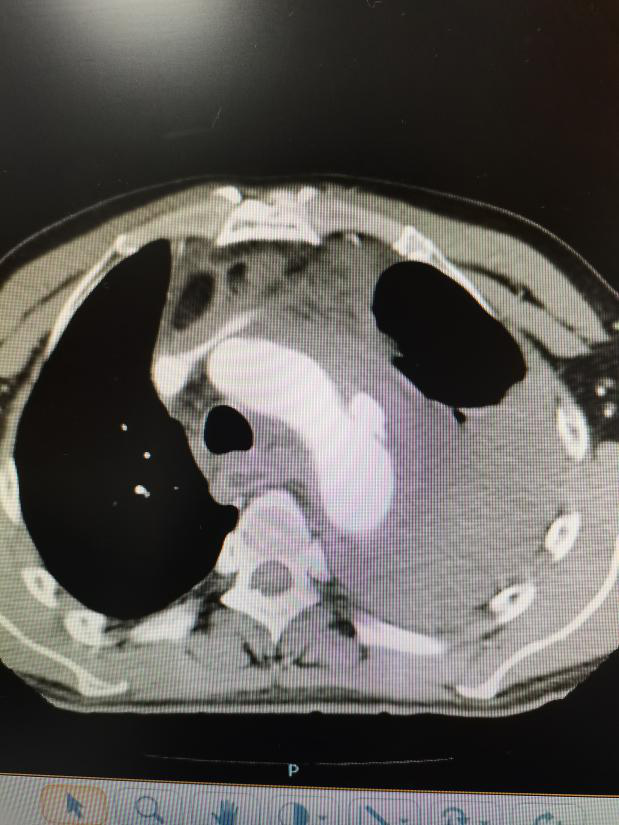

下午3時許,患者胸痛氣短癥狀加重,血壓從150mm Hg驟降至90mmHg,急診行胸部CT及主動脈CTA提示主動脈弓穿透性潰瘍,主動脈弓假性動脈瘤,縱隔及左側(cè)胸腔大量積液,考慮主動脈弓假性動脈瘤破裂出血迫入胸腔,患者病情告急!

▲主動脈CTA